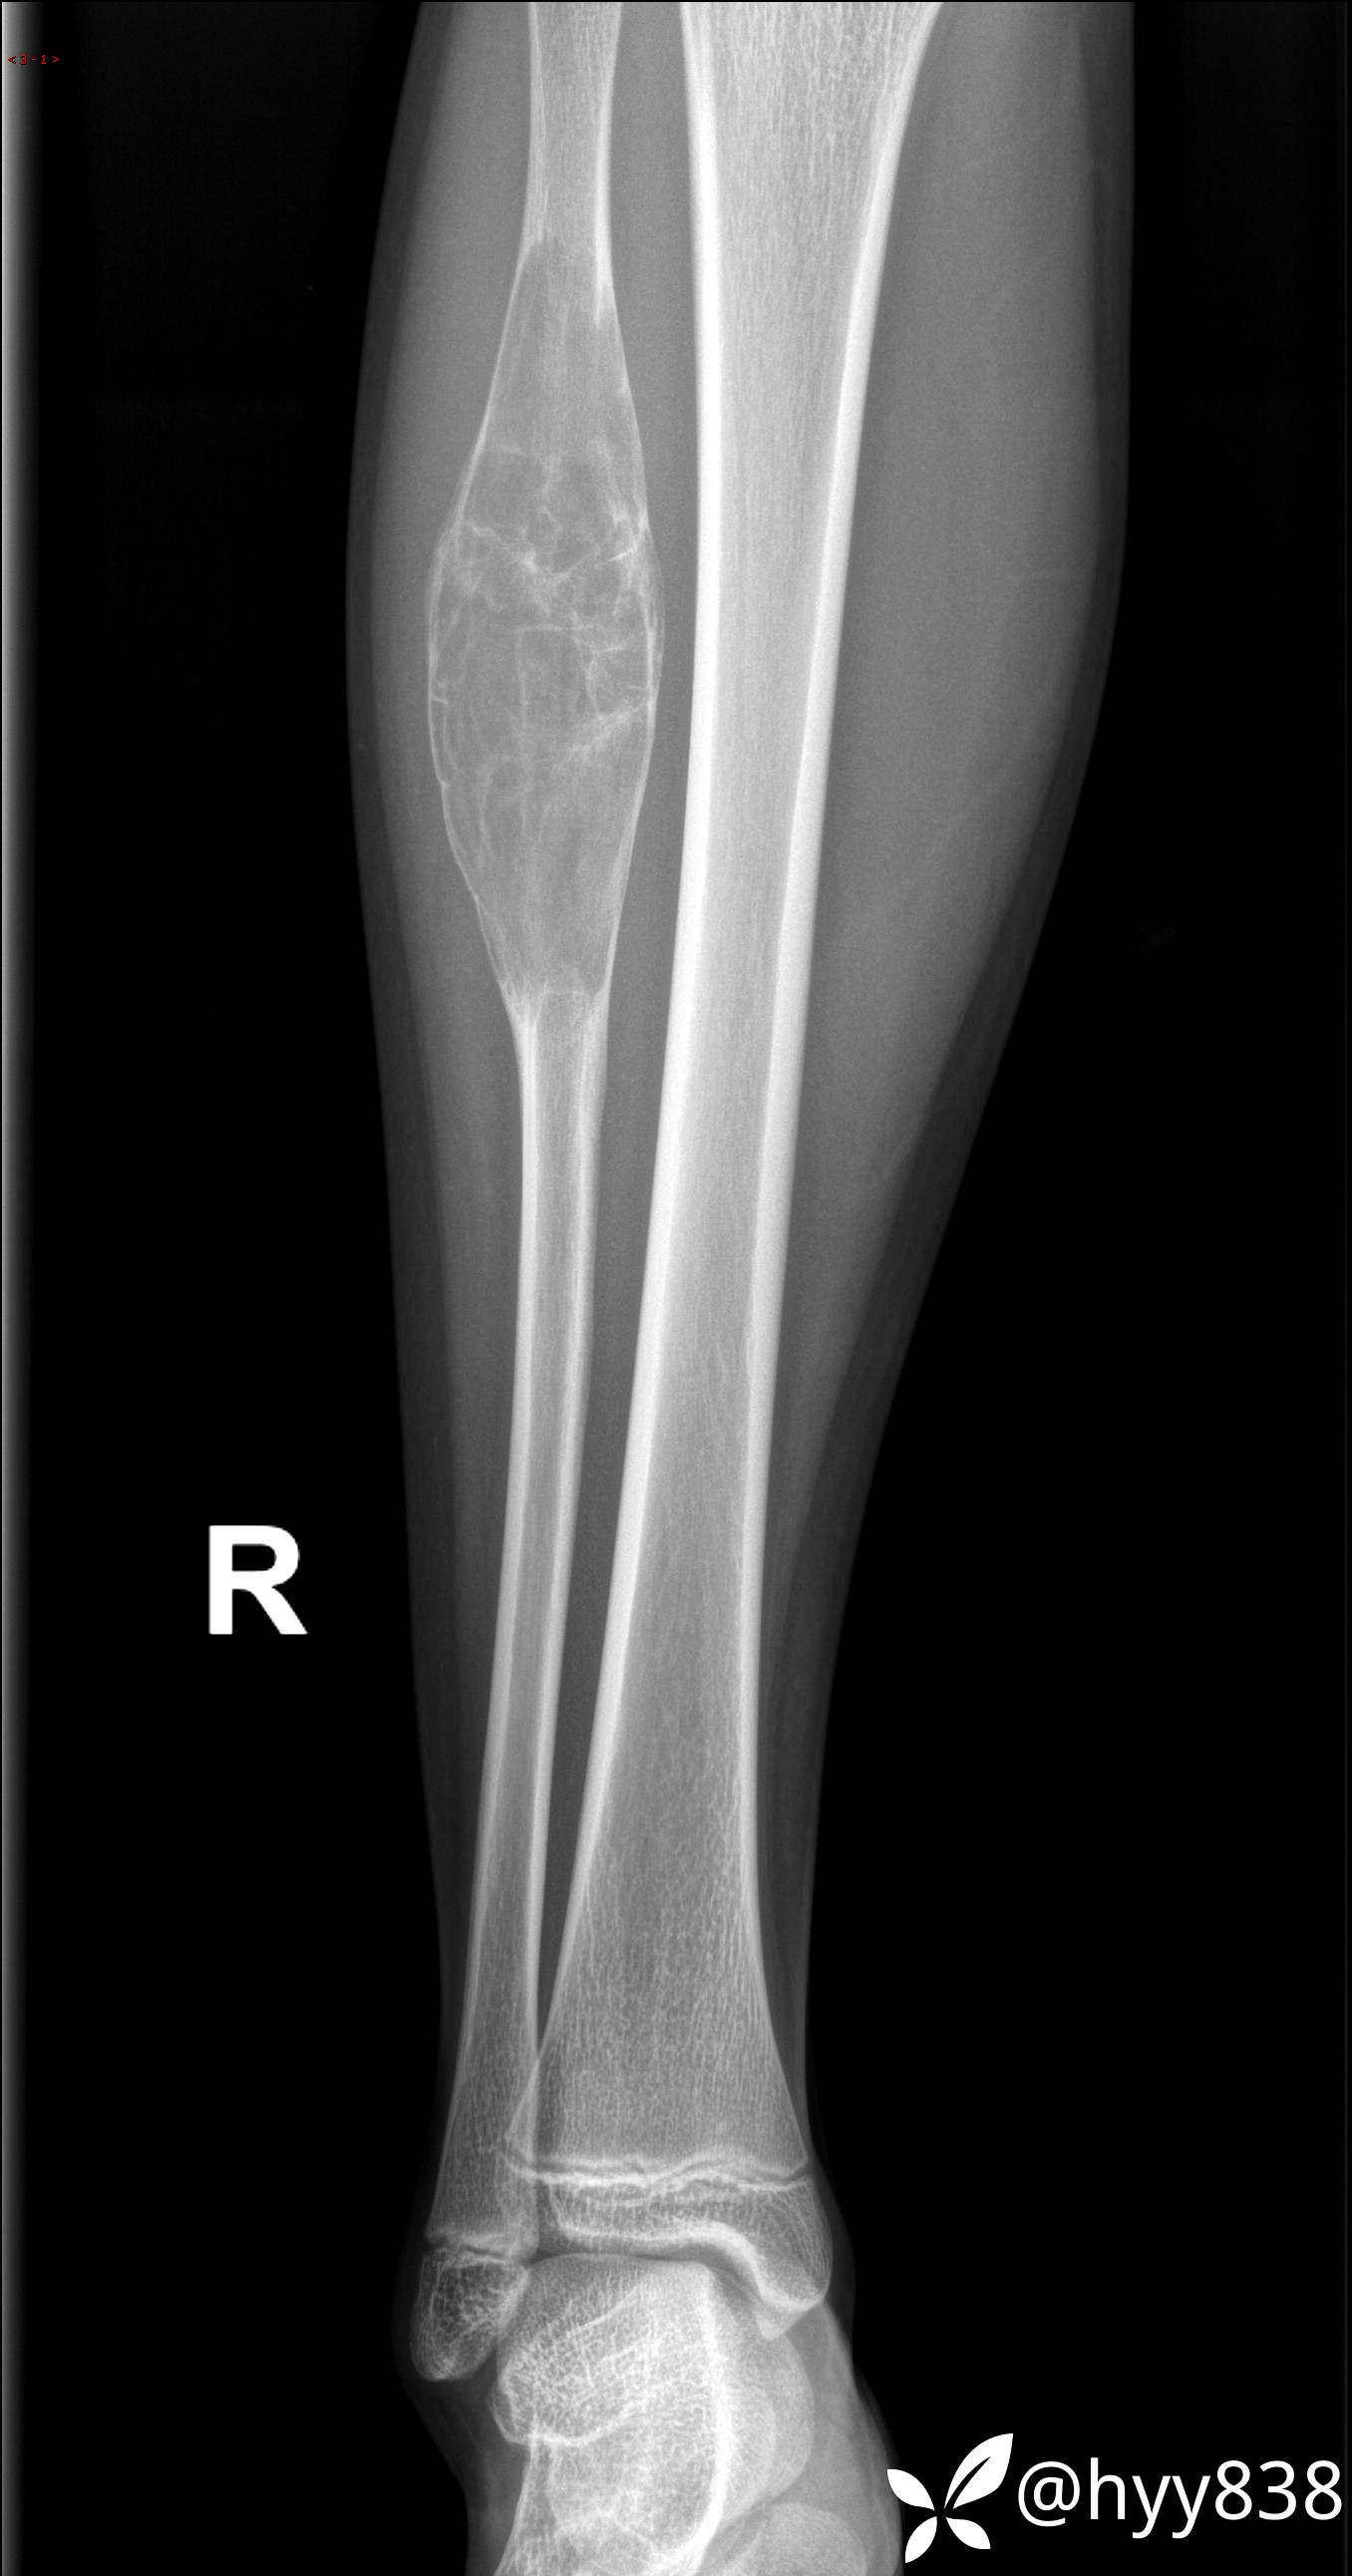

儿童,发现右小腿肿硬性肿物3年。资料齐全,ABC VS SBC VS FD--结果公布

主诉:发现右小腿肿硬性肿物3年

简要病史:患者3年前发现右小腿硬性肿物,按压稍疼痛,不伴活动受限及其他不适,后行胫腓骨MRI示:右腓骨上段肿物,考虑良性病变,现来院就诊,遂以“右下肢骨肿瘤”收入我科。 患者起病以来,精神良好,未进饮食,大小便正常,体重体力无明显改变。

临床诊断:胫骨肿物

平片